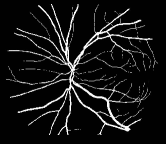

As pointed out in recent works [15, 17], a good semantic segmentation network should learn multi-level features. Further, it should have multiple stages with different receptive fields to learn more inherent features from different scales. FCN, taken as an example, uses skip connections to fuse multiple stages outputs, as well as the HED network, in which a series of side-output layers are added after each stage in VGGNet. The HED network was first proposed for edge detection, and further used for image-level vessel segmentation in recent studies [6, 16], with significant performance. However, our experimental results show that such network architecture is not appropriate for vessel segmentation directly. Figure 1 provides such an illustration. Reasons for this phenomenon are straightforward. On one hand, the side-output of the first layer often contains too many noises. On the other hand, the features produced by the last side-output layer are too coarse due to information loss of pooling operation. Obviously, the inaccurate vessel map of side-output1 and side-output4 should have negative impacts on the final segmentation result.

2.2 Bottom-top short connections

With the deepening of DSN network, the receptive field of each side-output layer gets larger, which makes the corresponding vessel map much blurrier as observed from the first row in Figure 1, especially for side-output4. These observations inspired us to pass low level fine semantic information to high levels to alleviate the blurring situation.

Bottom-top short connections aim to refine high-level segmentation results. However, we can observe from the first two rows in Figure 1 that the vessel map generated by the first side-output layer contains too many noises while the map generated by the last side-output could capture the main vessel structure. Therefore, we propose delivering high-level structural information to the first side-output layer to reduce its noises. We implemented this kind of information delivery by a top-bottom short connection from conv4 to feat_conv1, which can been seen in Figure 4. We first convolved the last convolution of conv4 using 1 convolution kernels with size 33. Then the obtained feature map are up-sampled 8 to get feat_4_1. The information (feat_4_1) passed from conv4 are concatenated with feat_conv1 to form feat_conv1_fuse (see Figure 5). At last, one hand hand, we perform a 11 convolution operation on feat_conv1_fuse to get the information (feat_1_2) delivered to feat_conv2. On the other hand, we performed convolution operation with a kernel size of 11 and sigmoid transformation for feat_conv1_fuse sequentially to obtain the segmentation result (side 1). At last, side 1 is compared with the ground truth to get the loss of the first side-output layer.

In addition, we can observe from Figure 1 that the side-output1 and side-output4 of the BTS-DSN were more accurate compared with those of the DSN.